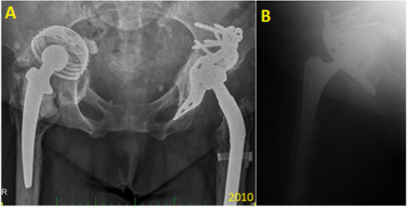

In our institution, 549 hips were re-implanted in the 4-year period from 2003 to 2007, with 243 of those re-implantations involving an acetabular component. BS plate was used in 78 (28.8%) of those latter cases, with only 8 of the patients being lost to follow-up. Also, in our institution, since 2000, we have preferred to perform non-cemented total hip replacements (THRs) in younger patients (under 70 years-old), and we have noted the need to perform re-implantation for subsequent defects, which tend to be larger, and especially so with the acetabular component (Figure 4). All patients with BS plate re-implantation were assessed by x-ray of the pelvis to identify cases of asymptomatic loosening; only 5 cases (7%) were found. In follow-up, the patients were re-operated (two times in total for 4.2% of the cases to address complete loosening or for an infectious complication in 2 cases (2.8%), with one needing full extraction of the BS plate. (Figure 5) provides an excellent representation of a case of the BS plate loosening itself.

Figure 5: Representative case of mechanical loosening of the BS plate. The proximal screws were fixed into defective bone, and a final revision was made by implantation of a hemispheric acetabular modulus. The final panel shows the results of the re-reimplantation (occurred and imaged in 2012).

The migration occurred proximally, with breakage of the proximal screws and migration of the plate (from 2009). Then, a mixture of the screws is seen in the bottom of the joint space (2010) and luxation (2012). In the same year (2012), we re-admitted the patient for re-reimplantation and implanted a hemispheric modulus with excenter and larger revision stem. In Figure 6, a case of mechanical loosening of the BS plate is presented. This event does not, generally, lead to positional plate loosening. Instead, the plate protrudes into the pelvis slightly, though it is still capable of full-weight bearing.